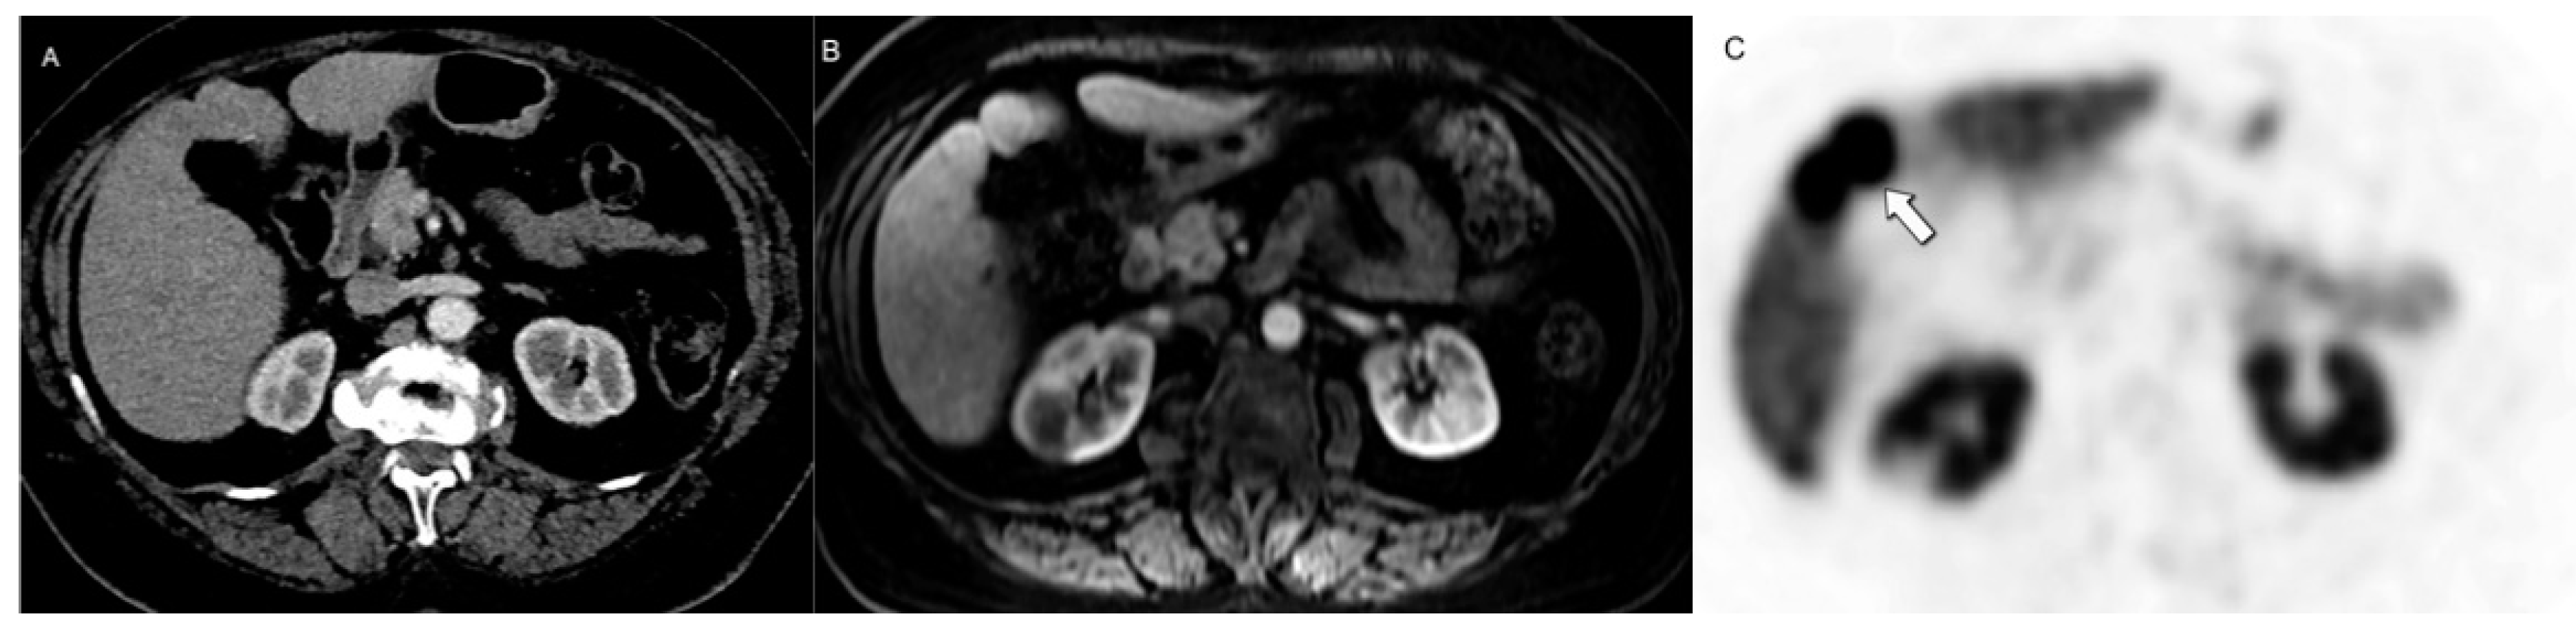

- Putzer, D.; Gabriel, M.; Henninger, B.; Kendler, D.; Uprimny, C.; Dobrozemsky, G.; Decristoforo, C.; Bale, R.J.; Jaschke, W.; Virgolini, I.J. Bone Metastases in Patients with Neuroendocrine Tumor: 68Ga-DOTA-Tyr3-Octreotide PET in Comparison to CT and Bone Scintigraphy. J. Nucl. Med. 2009, 50, 1214–1221. [Google Scholar] [CrossRef] [PubMed]

- Altieri, B.; Di Dato, C.; Martini, C.; Sciammarella, C.; Di Sarno, A.; Colao, A.; Faggiano, A. Bone Metastases in Neuroendocrine Neoplasms: From Pathogenesis to Clinical Management. Cancers 2019, 11, 1332. [Google Scholar] [CrossRef]

- Meijer, W.G.; Van Der Veer, E.; Jager, P.L.; Van Der Jagt, E.J.; Piers, B.A.; Kema, I.P.; De Vries, E.G.E.; Willemse, P.H.B. Bone Metastases in Carcinoid Tumors: Clinical Features, Imaging Characteristics, and Markers of Bone Metabolism. J. Nucl. Med. 2003, 44, 184–191. [Google Scholar]